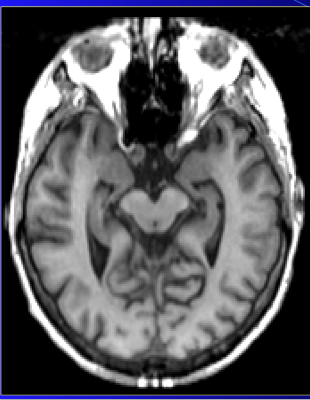

Is this T1 or T2?

T-1

T 1